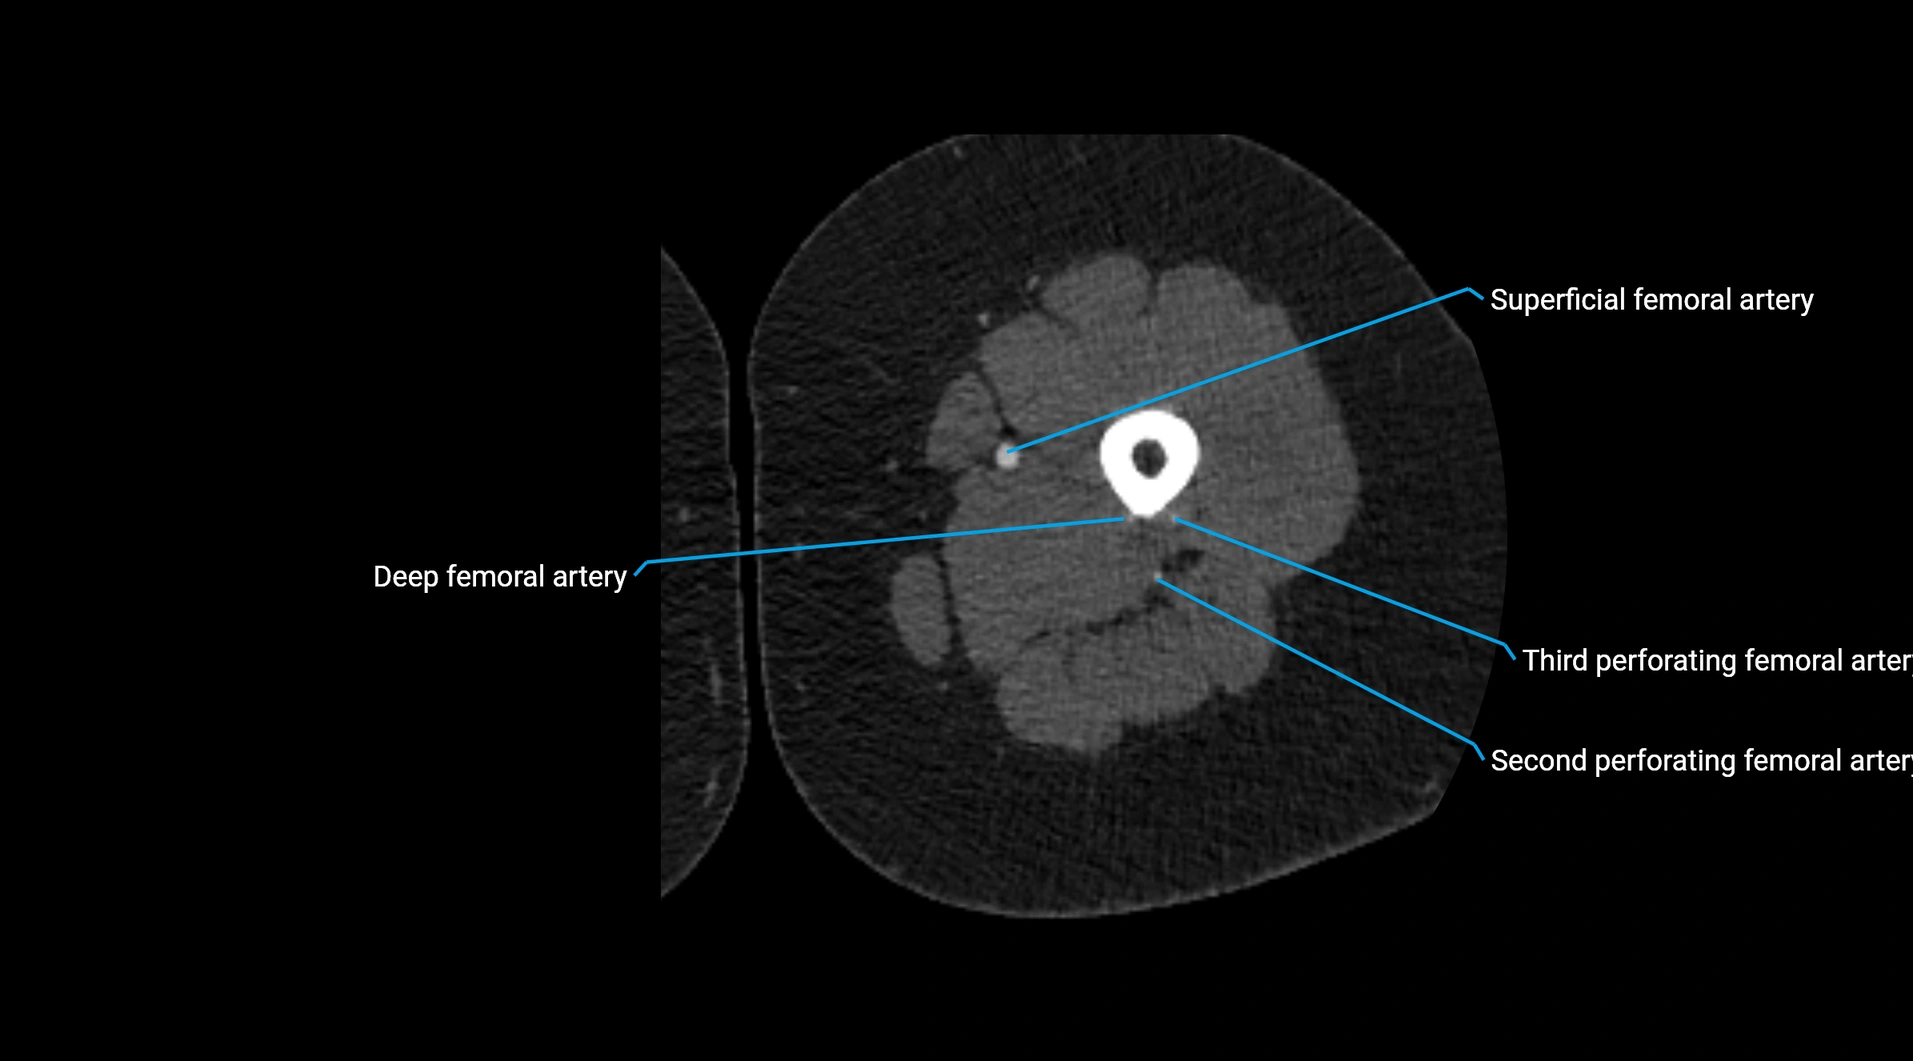

CT Appearance

Non-contrast CT:

• Appears as a tubular soft tissue structure anterior to vertebral bodies

• Calcified atherosclerotic plaques appear as hyperdense foci along the wall

• Useful for screening abdominal aortic aneurysm (AAA) size and mural calcification

Contrast-enhanced CT (CTA):

• Gold standard for abdominal aortic imaging

• Provides excellent detail of lumen, wall, aneurysm, thrombus, and branch vessels

• Multiplanar and 3D reconstructions help in aneurysm measurement, stent graft planning, and dissection evaluation

• Detects acute rupture, traumatic injury, or occlusion with high sensitivity